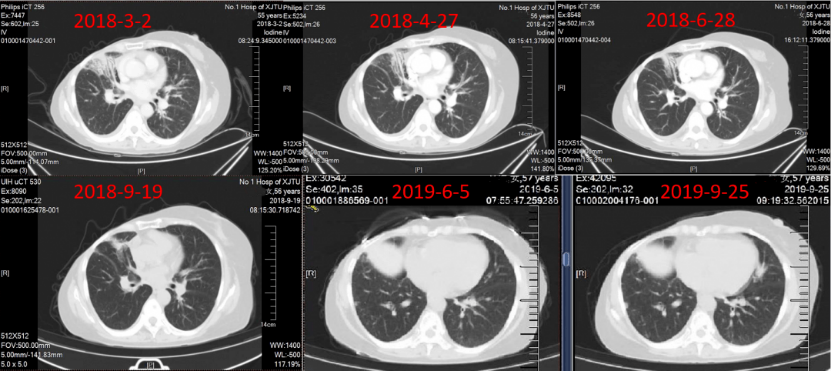

2017年10月25日~2018年2月22日,给予紫杉醇脂质体周疗×12+胸腔灌注×2+伽马刀立体定向治疗,疗效评价 部分缓解(PR)。2018年3月1日~2019年12月23日,给予氟维司群进行内分泌维持治疗,定期复查,病情稳定。

一线治疗PFS达到26个月,整体疗效评价PR(图4~7)。

图4:一线治疗期间胸部CT随访

图5:一线维持治疗期间随访胸部CT